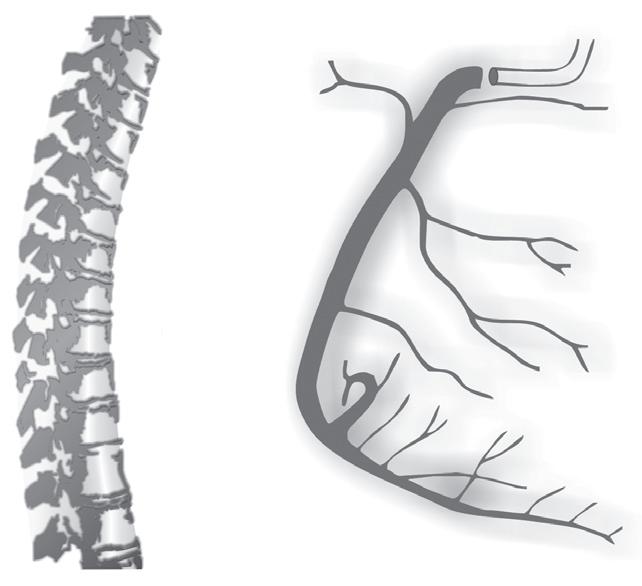

anatomia das artérias Coronárias

Ver Figuras 18.34 a 18.37

Não podemos terminar este capítulo de isquemia e lesão miocárdica sem abordar a ana tomia das artérias coronárias, a sua relação com as diversas estruturas cardíacas, a sua loca lização topográfica, assim como a correlação entre a obstrução da artéria e do local da artéria com as alterações agudas do segmento ST.

Na cardiopatia isquémica, não há qualquer correlação entre a depressão aguda do seg mento ST e a localização da artéria coronária envolvida, pelo contrário, quando há supra desnivelamento de ST (onda de lesão) verificamos que existe uma grande correlação entre, as respetivas derivações eletrocardiográficas onde está presente e a obstrução ou o sítio de obstrução da artéria coronária doente.

A artéria circunflexa (Cx) segue pelo sulco auriculoventricular esquerdo até ao sulco interventricular posterior. Esta artéria é dominante, isto é, ultrapassa este sulco e dá origem à descendente posterior em 15% dos casos.

Da artéria circunflexa originam ‑se três grandes artérias que denominamos obtusas margi nais, sendo estas os principais ramos da artéria circunflexa, que vascularizam a parede livre do ventrículo esquerdo. Para além da origem destas artérias obtusas marginais, a artéria circunflexa tem calibre pequeno. Da artéria circunflexa emergem um ou dois ramos para a aurícula esquerda. Estes ramos vão suprir a parte lateral e posterior da aurícula esquerda.

Artéria coronária direita

O ostium da artéria coronária direita (CD) tem origem na parte superior e ligeiramente anterior do seio coronário direito, junto à união sino tubular da aorta, ficando, no entanto,